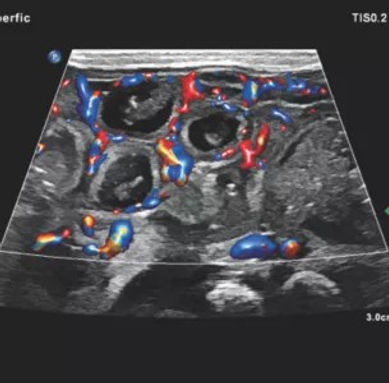

Diagnostic rapid și fără radiații: ideală pentru evaluarea mușchilor, tendoanelor, ligamentelor, articulațiilor — în timp real, în dinamică

Monitorizare continuă a vindecării: permite urmărirea evoluției inflamațiilor, edemelor, micro-rupturilor sau leziunilor cronice

Precizia tratamentelor prin ghidaj ecografic: infiltrații, terapii regenerative autologe, PRP, exozomi sau acid hialuronic – toate pot fi administrate cu acuratețe milimetrică, pentru eficiență maximă și risc minim